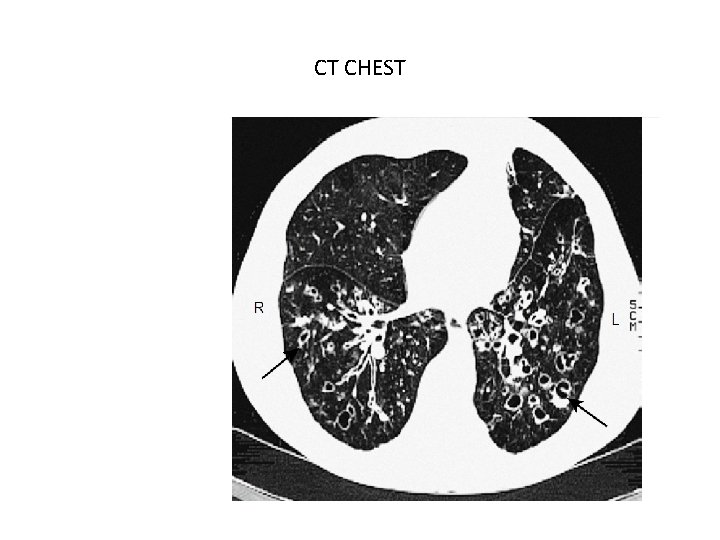

CT CHEST

q Investigations • Bacteriological and mycological examination of sputum • Radiological examination v C X ray v CT chest.